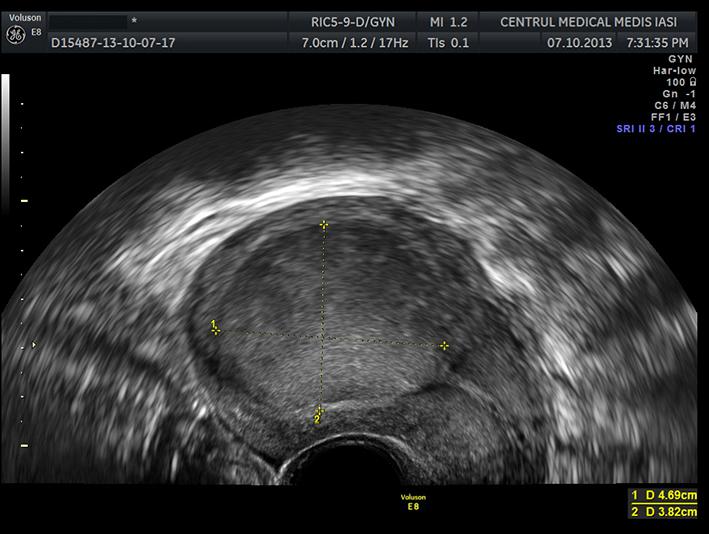

Procesul de diagnostic pe scurt și investigațiile uzuale

Evaluarea inițială implică anamneză, examen clinic și de obicei investigații imagistice; deciziile privind tratamentul se iau în funcție de dimensiune, aspect ecografic, simptomatologie și contextul general de sănătate.

• Imagistica și monitorizarea periodică sunt esențiale pentru a ghida deciziile și pentru a identifica cazurile care necesită investigații suplimentare.